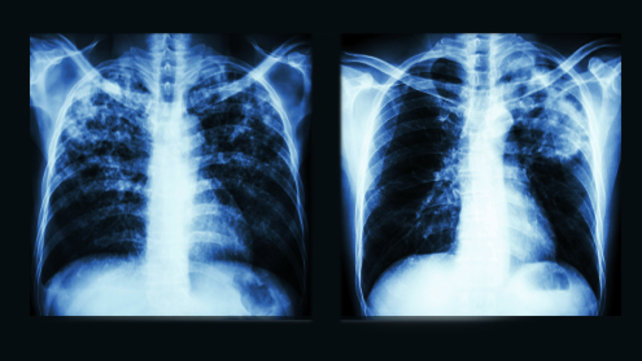

Tuberculosis (RISE Clinic)

The RISE Clinic at The Miriam Hospital provides specialty consultation related to tuberculosis (TB) care in partnership with the Rhode Island Department of Health.

Our experienced staff members know how to safely care for contagious patients. This includes treatment for those who have developed tuberculosis and for those persons who have been exposed and are at high risk of developing the disease in the future.

The RISE Clinic has about 8,500 patient visits each year. Though patients whom the clinic treats are infected with tuberculosis, most are not ill from the disease and are not contagious. The treatments provided are critical in order to eliminate the chances that these patients will ever get ill from TB or be able to pass TB on to others.